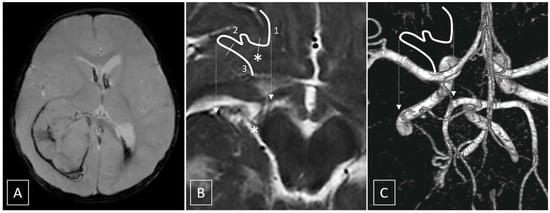

A preoperative three vessel angiography (bilateral internal carotid artery and dominant vertebral artery) confirmed the presence of a slightly enlarged right anterior choroidal artery feeding the tumoral blush. No feeders were observed from the posterior circulation; embolization was obtained with n-butyl cyanoacrylate (NBCA) superselective injection (0.4 mL) via a microcatheter (Magic 1.2F-Balt, Montmorency, France; aided by a microguidewire Hybrid 0.008-Balt, Montmorency, France) navigated near the tumor pedicle, distally, to the plexal point of the anterior choroidal artery (Figure 2). The positioning of the microcatheter distally, in the anterior choroidal artery, determined, as expected, a rectification of the artery, and a panoramic injection (guiding catheter Envoy 5F-Codman Neuro, Raynham, MA-positioned in the internal carotid artery) revealed an absence of flow within the anterior choroidal artery. The total time that elapsed between micro-catheterization, glue injection and retrieval of the microcatheter was 6 min. The subsequent control angiography revealed the exclusion of the tumor blush and a re-opening of the anterior choroidal artery. Total contrast media of 30 mL (300 mgI/mL), fluoroscopy time was 11 min, total series of 9, and cumulative DAP 20 710 mGycm2.

Figure 2. (A) Tumoral blush during superselective free-flow contrast injection in Frontal (F) and Lateral (L) views. (B) Forced injection of contrast media is performed to test for the presence of dangerous anastomosis. By comparison, with injection A, note the appearance of an additional vessel which corresponds to the course of the posterolateral choroidal artery. Unsubtracted images (small quadrants) of the final glue cast show penetration in the vascular bed of the tumor, and in the right posterolateral choroidal artery; penetration in the latter should be anticipated, even in the absence of enlarged posterior choroidal feeders, and should be carefully monitored to avoid potential complications.